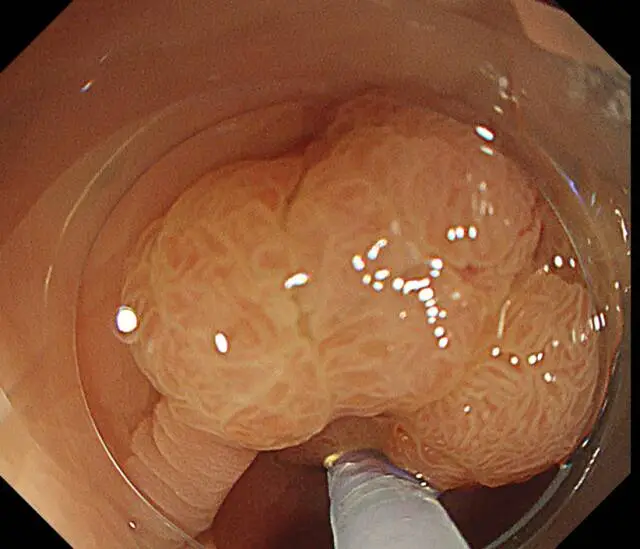

因为消化道早癌不仅“无症状”

在普通胃肠镜下同样很“隐匿”

只有通过胃肠镜精查

才能更好地发现早癌

更先进的检查设备

新镜界引进国际尖端的奥林巴斯X1(CV1500)内镜系统,搭载第三代NBI窄带成像、4K超高清成像技术等,同时所有患者全部采用放大内镜放大精查,这些技术、设备可以清晰观察黏膜微血管形态、腺管开口结构,使微小的凹凸不平和组织边界更加清晰,让消化道早癌无所遁形。